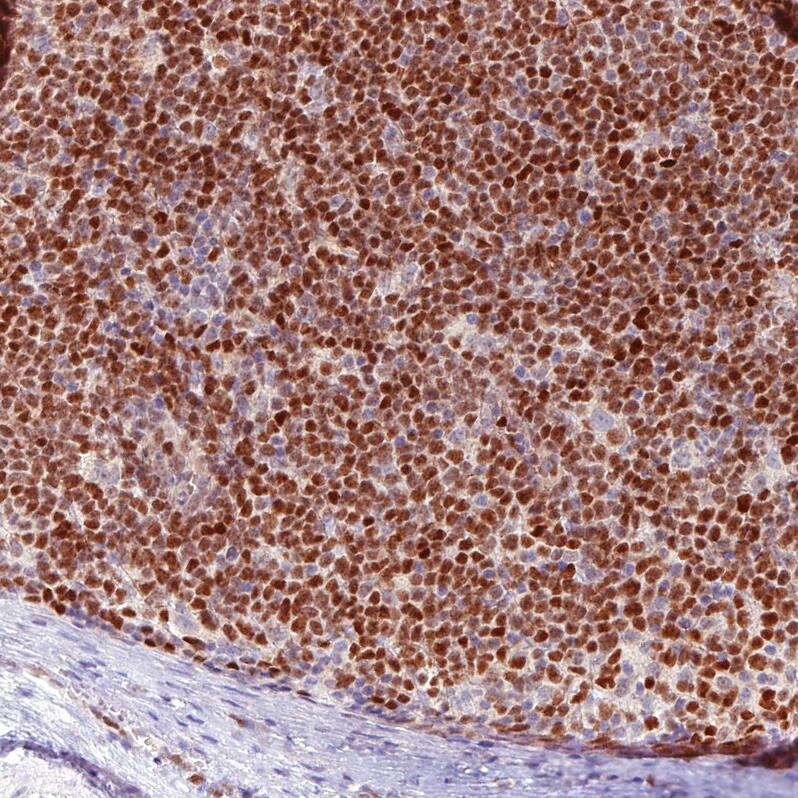

Immunohistochemistry-Paraffin: SOX11 Antibody [NBP3-43927]

Staining of human mantle cell lymphoma shows moderate to strong nuclear positivity in tumor cells.